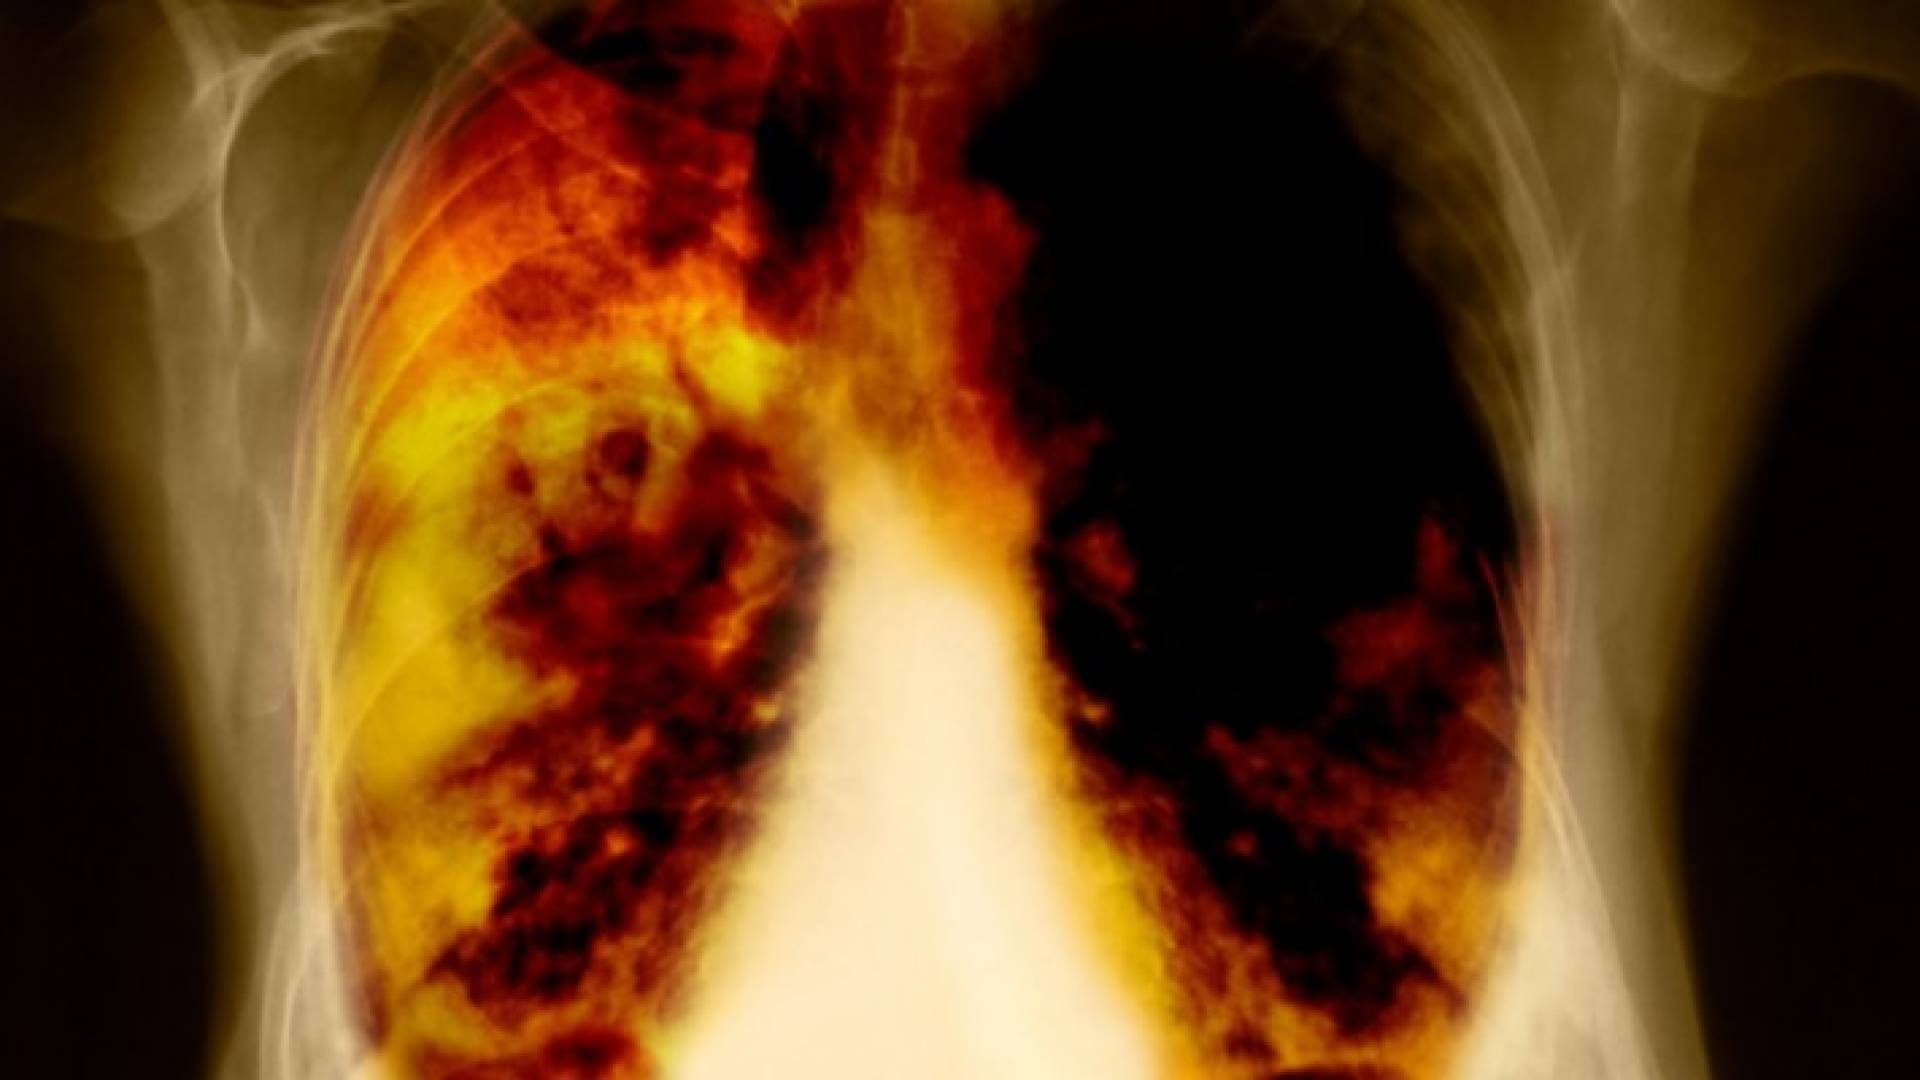

الدهون المشبعة قد تسبب سرطان الرئة

رجحت دراسة أجريت في الآونة الأخيرة أن يزيد خطر الإصابة بسرطان الرئة بين من يتناولون الكثير من الدهون المشبعة، وهو نوع "سيئ" من الدهون موجود بكثرة في أطعمة مثل الزبد ولحوم الأبقار.

ووجدت الدراسة أن احتمال إصابة من يتناولون دهونا مشبعة بأمراض خبيثة في الرئة يزيد ١٤% عمن لا يتناولون دهونا كثيرة في طعامهم.